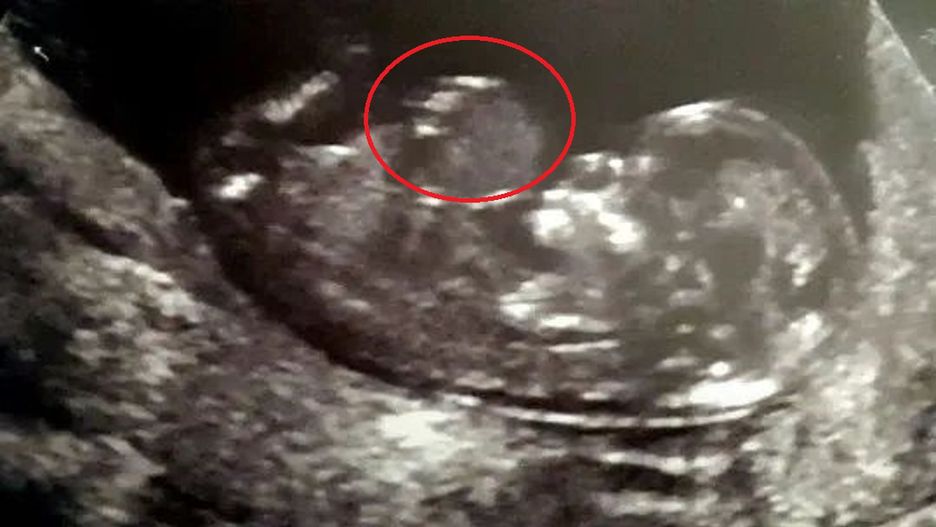

Kiedy Kelly i Sean Phizacklea wybrali się na badanie w 12. tygodniu ciąży, dowiedzieli się, że niektóre narządy ich nienarodzonego dziecka rosną poza jego ciałem. Dziecko miało poważną przepuklinę pępowinową — stan, który występuje, gdy ściana brzucha dziecka nie tworzy się w czasie ciąży.

USG Kelly

USG Kelly © Facebook